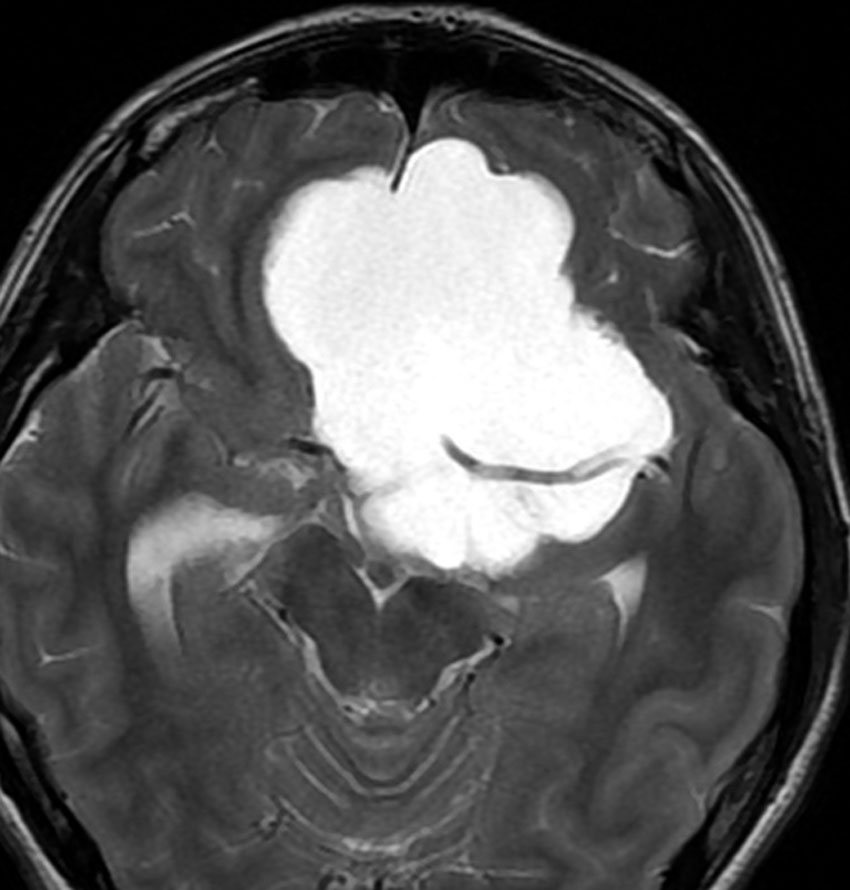

鞍隔膜上 supradiaphragmic type

この子の症状は頭痛だけ。両親はなぜ気づかなかったのかと疑問を持ちますが,巨大になるまで症状が出ないこともあるのです。左のCTで腫瘍の周囲にバラバラと白い点状の石灰化があるので診断できます。左の視床下部から発生したクラニオでした。開頭手術しますが超高難易度です,怖いです (┯_┯) 複数回開頭手術になりましたが結果的に全摘出できています (by Dr 山本哲哉)。

危険な のう胞性 頭蓋咽頭腫 cystic craniopharyngioma

上に示した例は,巨大な「のう胞性」頭蓋咽頭腫でもあります。袋の中に液体が入っているのを「嚢胞 cyst」といいます。大部分は液体なので,袋を破れば腫瘍は簡単に小さくなります。